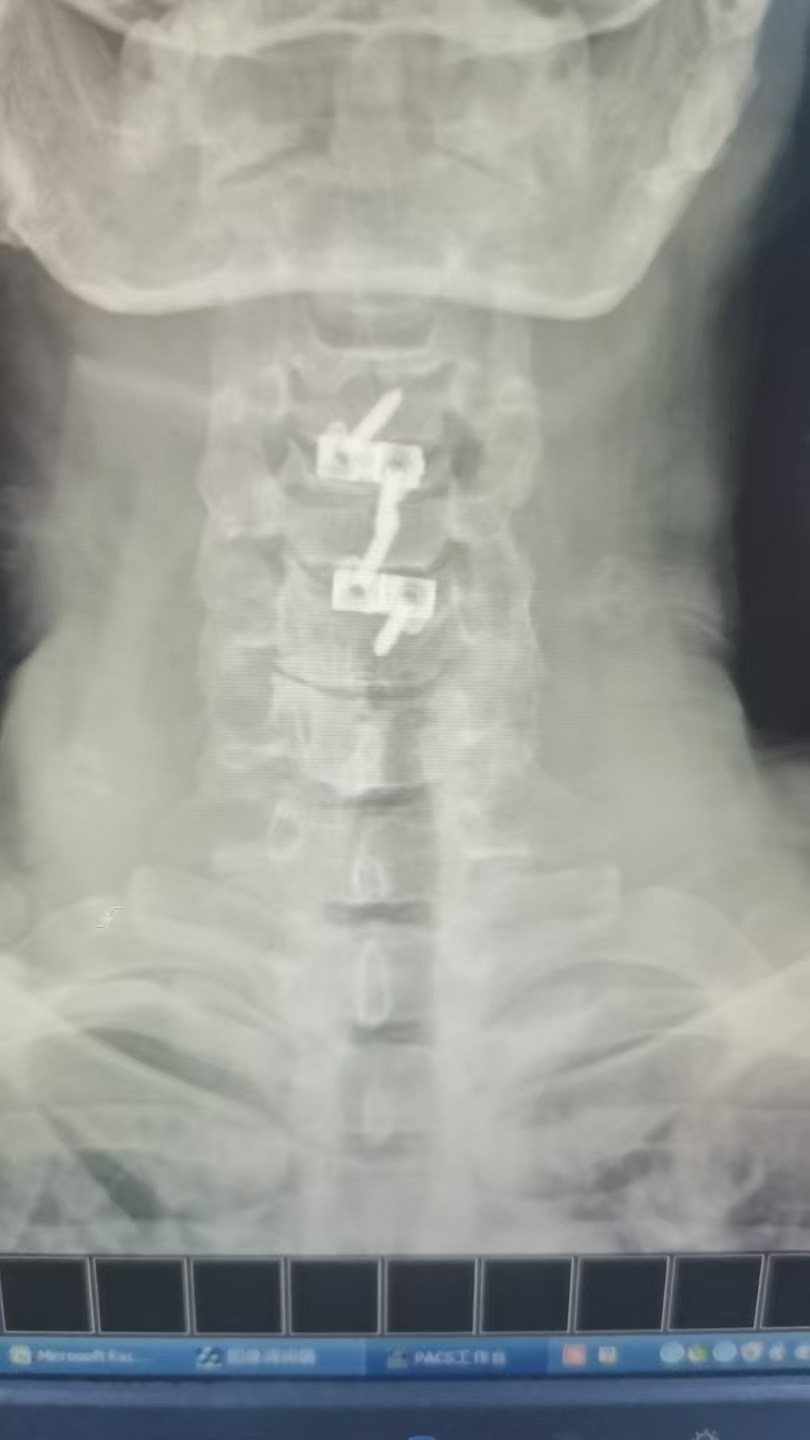

47岁李先生(化名)近日因车祸导致“颈髓损伤,四肢麻木无力”入院。经我院脊柱外科团队详细检查,影像学检查显示颈3/4及4/5节段椎间盘突出,脊髓神经根受压,引发四肢不完全瘫痪。术前右侧上、下肢体肌力:3级,左上肢肌力3级,左下肢肌力1级。

由于保守治疗效果不明显,医护团队综合评估后,决定为患者施行颈椎前路微创手术。在南医三院派驻骨科专家、东凤人民医院副院长闫慧博(挂职)的带领下,我院骨科团队共同为患者实施“颈椎3/4、4/5双节段前路椎间盘摘除+椎体融合术”。

手术借助进口微创设备完成,切口小,术中出血约20ml,历时约1.5小时,患者生命体征平稳。

(术后图)

患者术后1小时意识清醒,生命体征稳定。术后神经功能较前有所改善,特别是右侧肢体肌力已达4级,为早期开展精细活动和力量训练创造了良好条件。